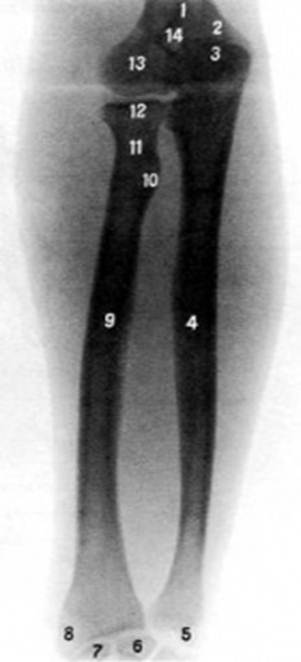

S: Цифра 9 указывает на … лучевая кость

S: Цифра 4 указывает на локтевая кость

S: На рентгеновском снимке изображен articulatio cubiti (латинский язык).